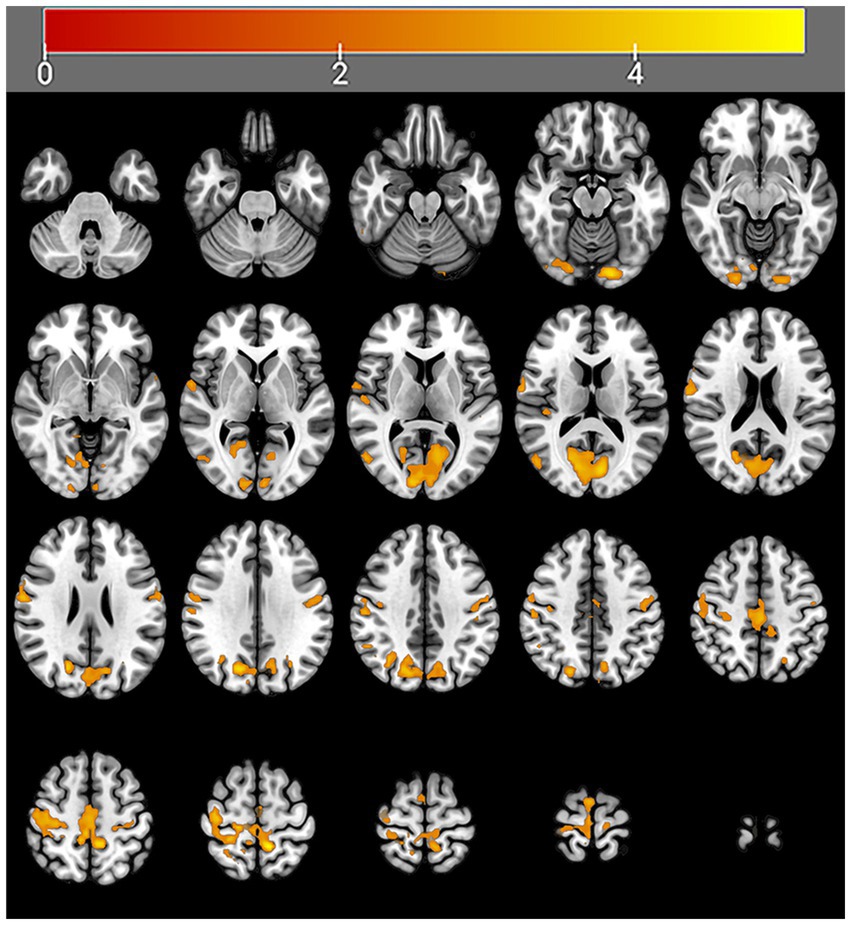

After 4 weeks of taVNS treatment, the mALFF value in the sensorimotor network (SMN) brain regions (Precentral_R, Rolandic operculum_R, Postcentral gyrus_Bi, Paracentral_Bi, Supplementary motor areas_Bi and Middle cingulate gyrus_L), default mode network (DMN) brain regions (Precentral_R, Rolandic operculum_R, Postcentral gyrus_Bi, Paracentral_Bi, Supplementary motor areas_Bi and Middle cingulate gyrus_L), and visual network (VN) brain regions (Lingual gyrus_L, Superior occipital gyrus_L, Cuneus_L and Calcarine_Bi) of the treatment group was significantly greater than that before the treatment (Table 4 and Figure 6). In contrast, the mALFF in the right hippocampus decreased post-treatment (Table 4 and Figure 7).

Table 4

| Group | Contrast | Cluster | Voxel-size | Brain region | Peak T-value | MNI coordinates | ||

|---|---|---|---|---|---|---|---|---|

| X | Y | Z | ||||||

| Treatment group | Post>Pre | Cluster 1 | 53 | Lingual gyrus_L | 4.98 | −15 | −87 | −15 |

| Cluster 2 | 469 | Calcarine_Bi | 5.16 | −9 | −81 | 12 | ||

| Cuneus_Bi | ||||||||

| Precuneus_R | ||||||||

| Cluster 3 | 96 | Rolandic operculum_R | 4.57 | 66 | −3 | 15 | ||

| Cluster 4 | 49 | Precuneus_L | 4.02 | −15 | −66 | 36 | ||

| Cuneus_L | ||||||||

| Superior occipital_L | ||||||||

| Cluster 5 | 227 | Postcentral_Bi | 4.48 | 39 | −15 | 60 | ||

| Precentral_R | ||||||||

| Cluster 6 | 225 | Paracentral_Bi | 4.86 | −12 | −45 | 60 | ||

| SMA_Bi | ||||||||

| Middle cingulum_L | ||||||||

| Post<Pre | Cluster 1 | 6 | Hippocampus_R | 5.12 | 39 | −30 | −9 | |

| Control group | Post>Pre | No brain region above the threshold. | ||||||

| Post <Pre | No brain region above the threshold. | |||||||

Regions showing significantly increased mALFF values after taVNS treatment compared with “before treatment,” controlling for age as a covariate (voxelwise, P < 0.05, uncorrected; clusterwise, P < 0.05, FDR corrected).

mALFF, mean amplitude of low-frequency fluctuation (mALFF); taVNS, transcutaneous auricular vagus nerve stimulation; SMA, supplementary motor area.

Figure 6

Regions with increased brain activity in the treatment group after 4 weeks of taVNS treatment. Color intensity (yellow) corresponds to the magnitude of the increase in activity in these brain regions.